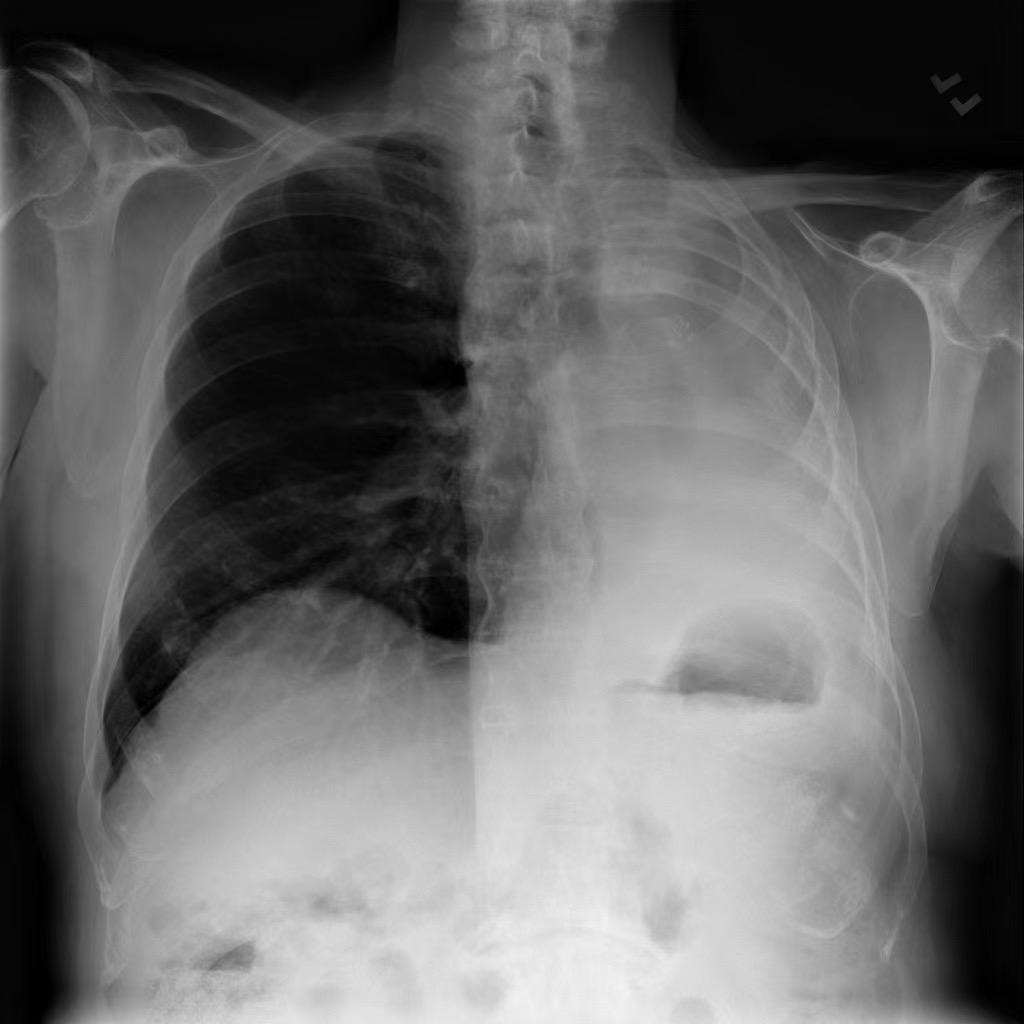

Refer to caption

Figure 1: An overview of PASS. Given a multimodal complex reasoning task (CXR image, textual comprehensive query, multimodal personalized context), our probabilistic controller learns a continuous task-conditioned distribution over the agentic supernet (i.e. a directed acyclic graph of medical agent containers). At each step, it samples an action, yielding a workflow annotated with interpretable probabilities for post-audits and directly enhances clinical AI safety. Tool outputs, which can be both text and images, are summarized and fed into an evolving personalized memory and shared in-context to inform subsequent steps. The controller is trained via a principled three-stage strategy (expert knowledge warm-up, contrastive path ranking, cost-aware reinforcement learning) to optimize the accuracy-cost trade-off. Eventually, PASS is enabled to answer multimodal medical questions in free-form text via an interpretable, adaptive, and efficient agentic reasoning process.

Image: ‘images/source0001.jpg’ Question: Based on the chest X-ray provided, identify and locate any abnormalities within the pleural spaces, particularly focusing on the right lung and the lower left chest region. Determine if there is evidence of pleural effusion and evaluate its extent in these areas. Establish the relationship between the effusion in the right lung and the lower left chest region, explaining any potential underlying causes and clinical significance of these findings. Answer: The chest X-ray reveals a pleural effusion affecting the right lung and extending into the lower left chest region. The effusion is characterized by fluid accumulation in the pleural space, particularly notable on the right side. The relationship between the findings suggests that the effusion is more pronounced on the right, potentially indicating a unilateral process or a difference in fluid dynamics between the lungs. The clinical significance of these findings could be related to conditions such as infection, heart failure, or malignancy, which need to be further investigated through clinical correlation and possibly additional diagnostic tests. Required Tools: ‘ChestXRaySegment → ChestXRayClassify → VQAnalyze → ChestXRayReport → EarlyStop’